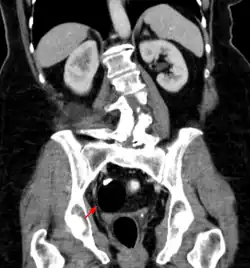

Les tératomes immatures de l’ovaire, souvent détectés à l'échographie, TDM ou IRM[21] sont potentiellement malins tout comme les tératomes testiculaires, qui sont généralement moins bien différenciés (donc avec un pronostic plus sombre). Des effets hormonaux, systémiques ou éloignés (ex. : encéphalite limbique paranéoplasique, encéphalite paranéoplasique anti-NMDAr)[22] sont possibles. Les métastases sont rares mais possibles (ex. : métastases neuroïdes matures d’un tératome ovarien[23]). Après ablation, des récidives sont possibles[24].